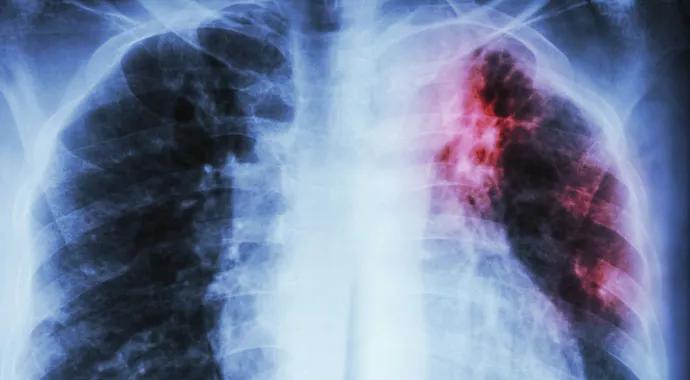

Idiopathic pulmonary fibrosis (IPF) is an incurable and fatal fibrotic lung disorder characterized by excessive connective tissue accumulation and scar formation, creating a cycle of progressive lung deterioration. In the United States, IPF affects between 132,000 and 200,000 people. Approximately 50,000 new cases are diagnosed each year and as many as 40,000 Americans die from IPF each year.